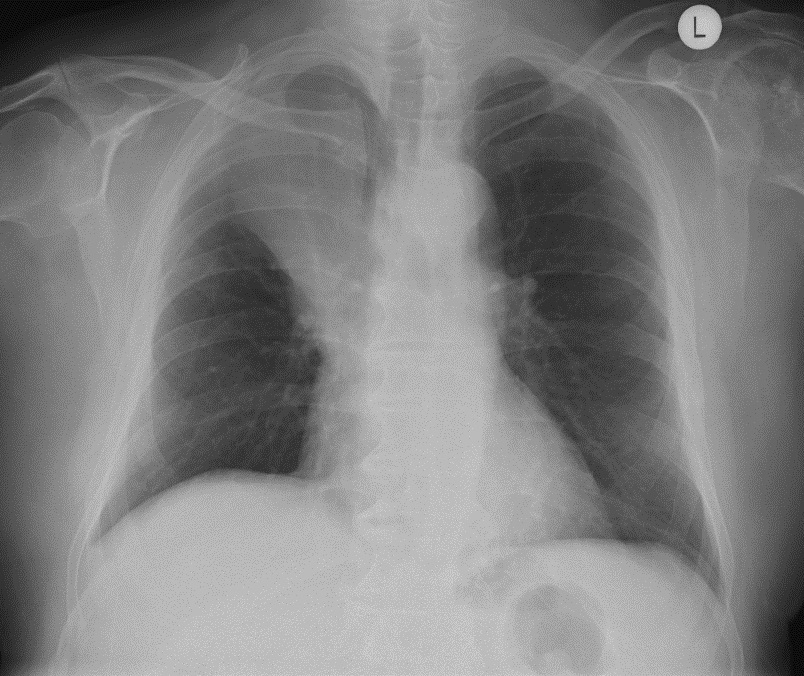

Left lower lobe atelectasis

The heart slightly rotates and the left hilum is pulled down. The flat waist sign describes the flattenin of the left heart border as a result of downward shift of hilar structures and resultant cardiac rotation.